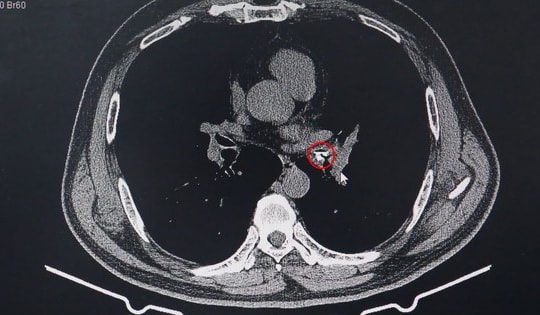

Bé trai ho mãi không khỏi, đi khám mới biết hóc hạt na trong phế quản

Bé trai bị ho liên tục trong 2 tháng, điều trị nhiều đợt kháng sinh nhưng không khỏi, đến khi chụp CT mới phát hiện dị vật trong đường hô hấp.